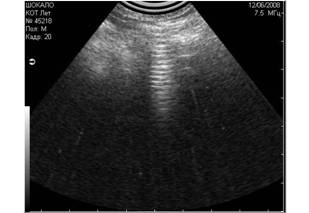

- вызванные плохим качеством выбривания кожи животного (Рис.3);

Рис3. Помехи, вызванные плохим выбриванием животного (продольные полосы слева). |